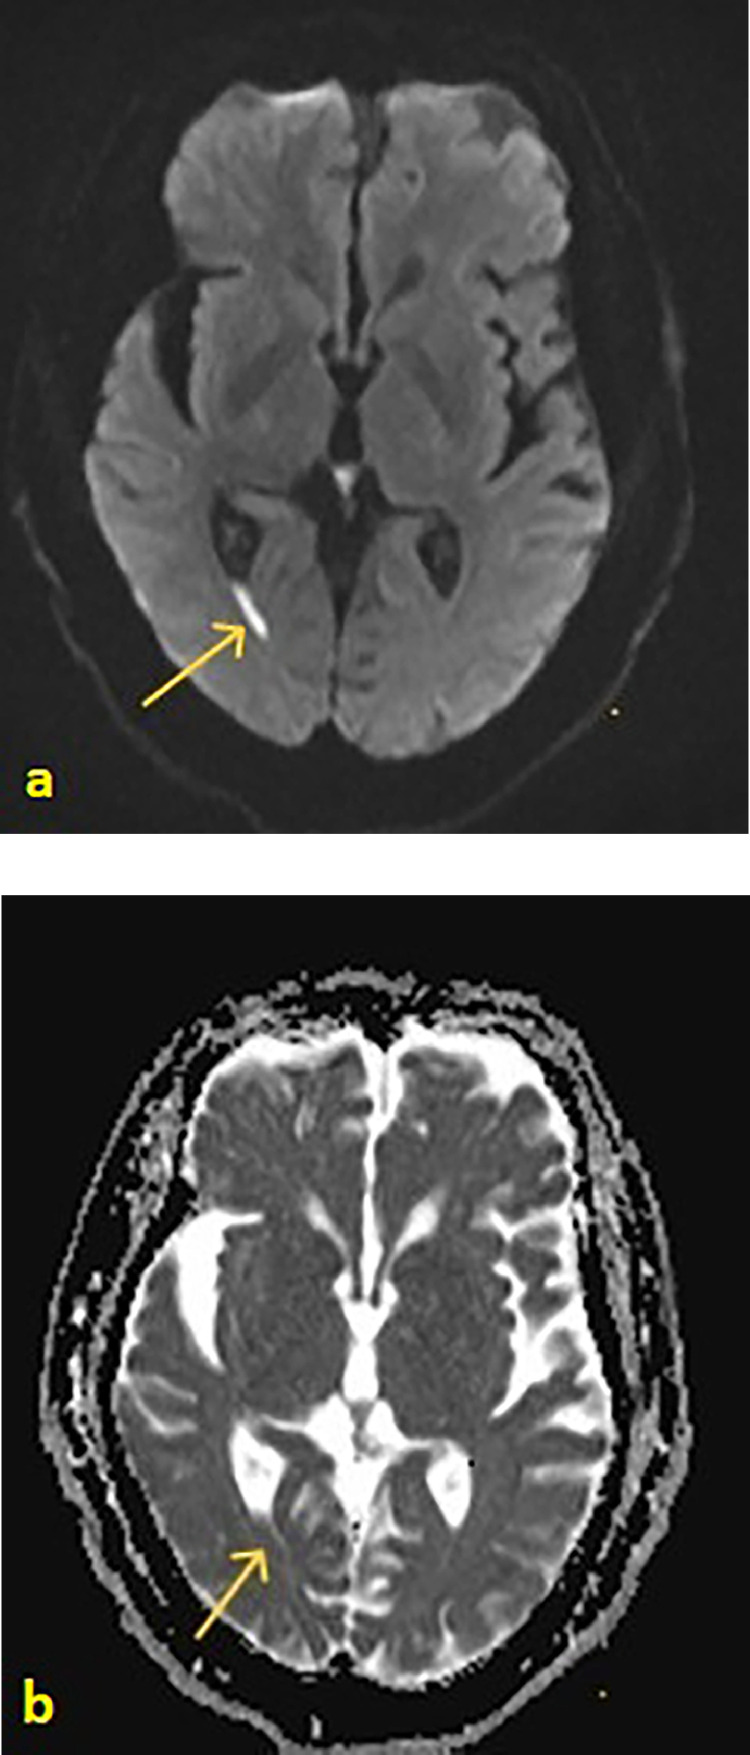

我们报告一例74岁女性头痛,发热,并间歇性右侧耳漏和鼻漏。她的鼻分泌物β -2-转铁蛋白检测呈阳性,证实脑脊液(CSF)泄漏。高分辨率CT (HRCT)显示右侧乳突、中耳和乳突空气细胞内的脑脊液缺损。钆增强脑MRI示侧脑室枕角弥散加权成像(DWI)高信号,DWI-表观弥散系数(DWI- adc)低信号,与脑室炎一致。经过六周的抗生素静脉注射后,她平静地康复了。病人接受手术修复骨缺损以防止复发。这是一例罕见的脑室炎合并自发性脑脊液泄漏的病例,没有现有的诊断标准,死亡率高。高临床怀疑辅助适当的影像学和多学科的方法来管理是必不可少的。

We present a case of a 74-year-old woman with headaches, pyrexia and intermittent right-sided otorrhoea and rhinorrhoea. Her nasal discharge tested positive for beta-2-transferrin, confirming a cerebrospinal fluid (CSF) leak. High-resolution CT (HRCT) mastoids showed a defect in the right tegmen, and CSF within the middle ear and mastoid air cells. A gadolinium-enhanced MRI brain showed high signal in the occipital horns of the lateral ventricles with diffusion-weighted imaging (DWI) and a low signal with DWI-apparent diffusion coefficient (DWI-ADC), consistent with ventriculitis. She made an uneventful recovery after 6 weeks of intravenous antibiotics. The patient had surgical repair of bony defects to prevent recurrence. This highlights a rare case of ventriculitis associated with a spontaneous CSF leak, with no existing set diagnostic criteria, and high mortality. High clinical suspicion aided by appropriate imaging, and a multidisciplinary approach to management are imperative.